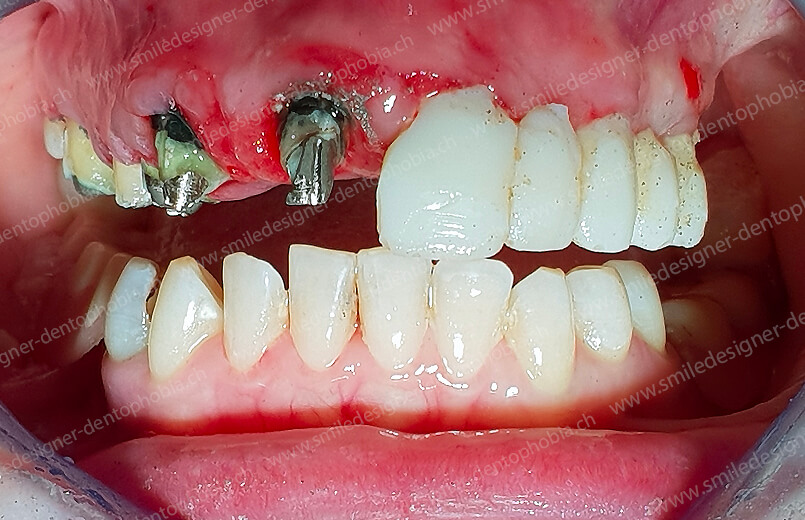

Cas clinique « DAMAGE CONTROL MCI » maxillaire : Bridge implanto-porté avec extensions postérieures (ALL ON 8) au maxillaire et à la mandibule. Version définitive des bridges avec un cosmétique en céramique.

BRIDGE RÉSILIENT DE PREMIÈRE INTENTION DE MISE EN CHARGE IMMÉDIATE POUR UNE RESOCIALISATION IMMÉDIATE DE LA PATIENTE

CAS EN COURS D’OSTEOINTÉGRATION DES IMPLANTS.